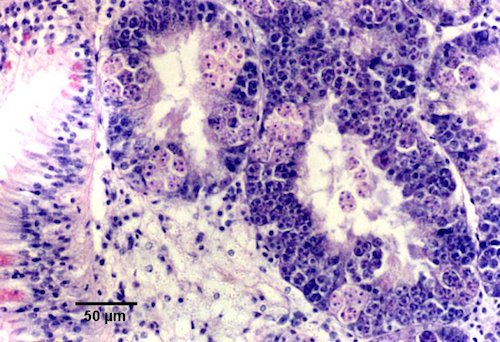

Fotos de histología tomadas de